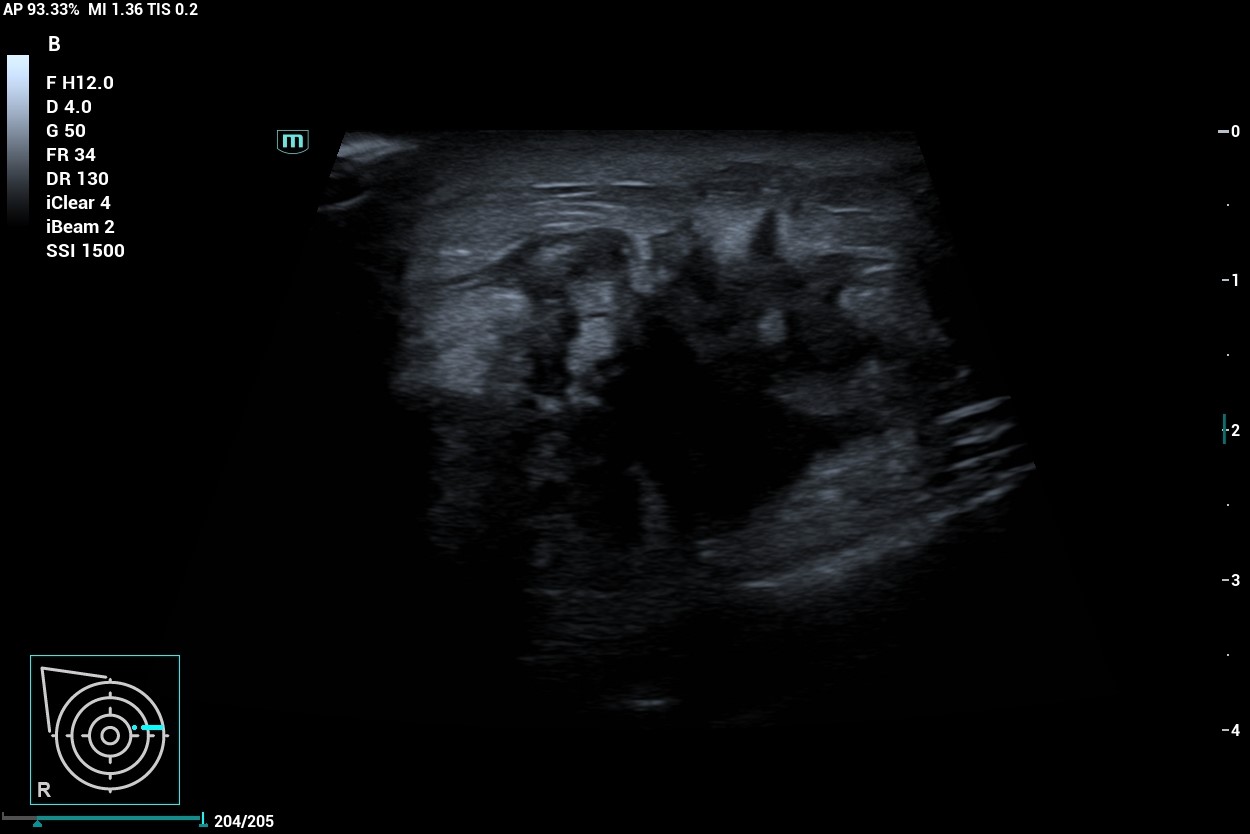

Al realizar ecografía observamos una imagen de 30 mm en cuadrantes internos de mama derecha que presenta bordes espiculados y contenido heteroecoico en su interior con áreas hipoecoicas.

Al tratarse de una lesión que presenta características de probable malignidad no solo en la exploración y anamnesis de la paciente sino a la confirmación con la ecografía, decidimos derivar a la paciente a Ginecología mediante circuito rápido, donde se confirma el diagnóstico de carcinoma ductal infiltrante de mama derecha G2, luminal B cT4bN3bM0.